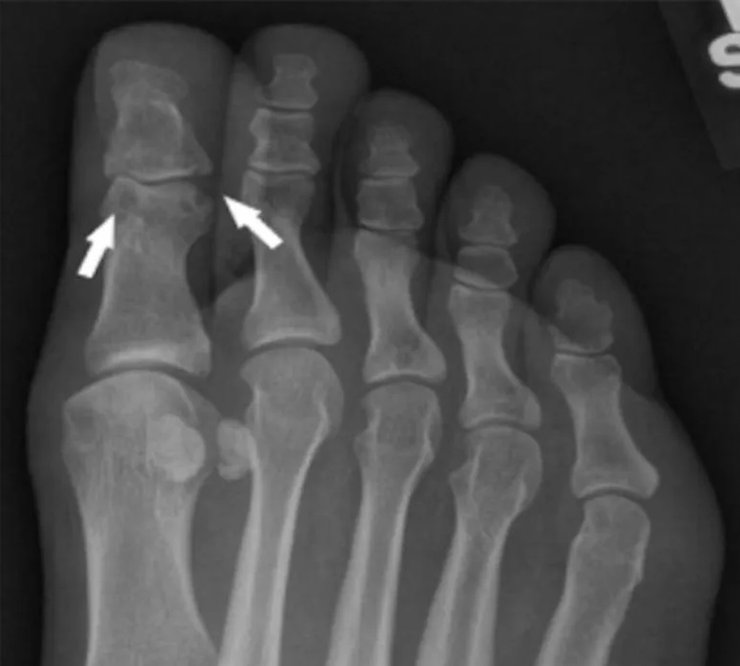

рентген стопы

На рентгенограмме стопы больного выявлены вдавленные эрозии суставов на большом пальце стопы, характерные для подагры.

Фото: UC San Diego Health Sciences